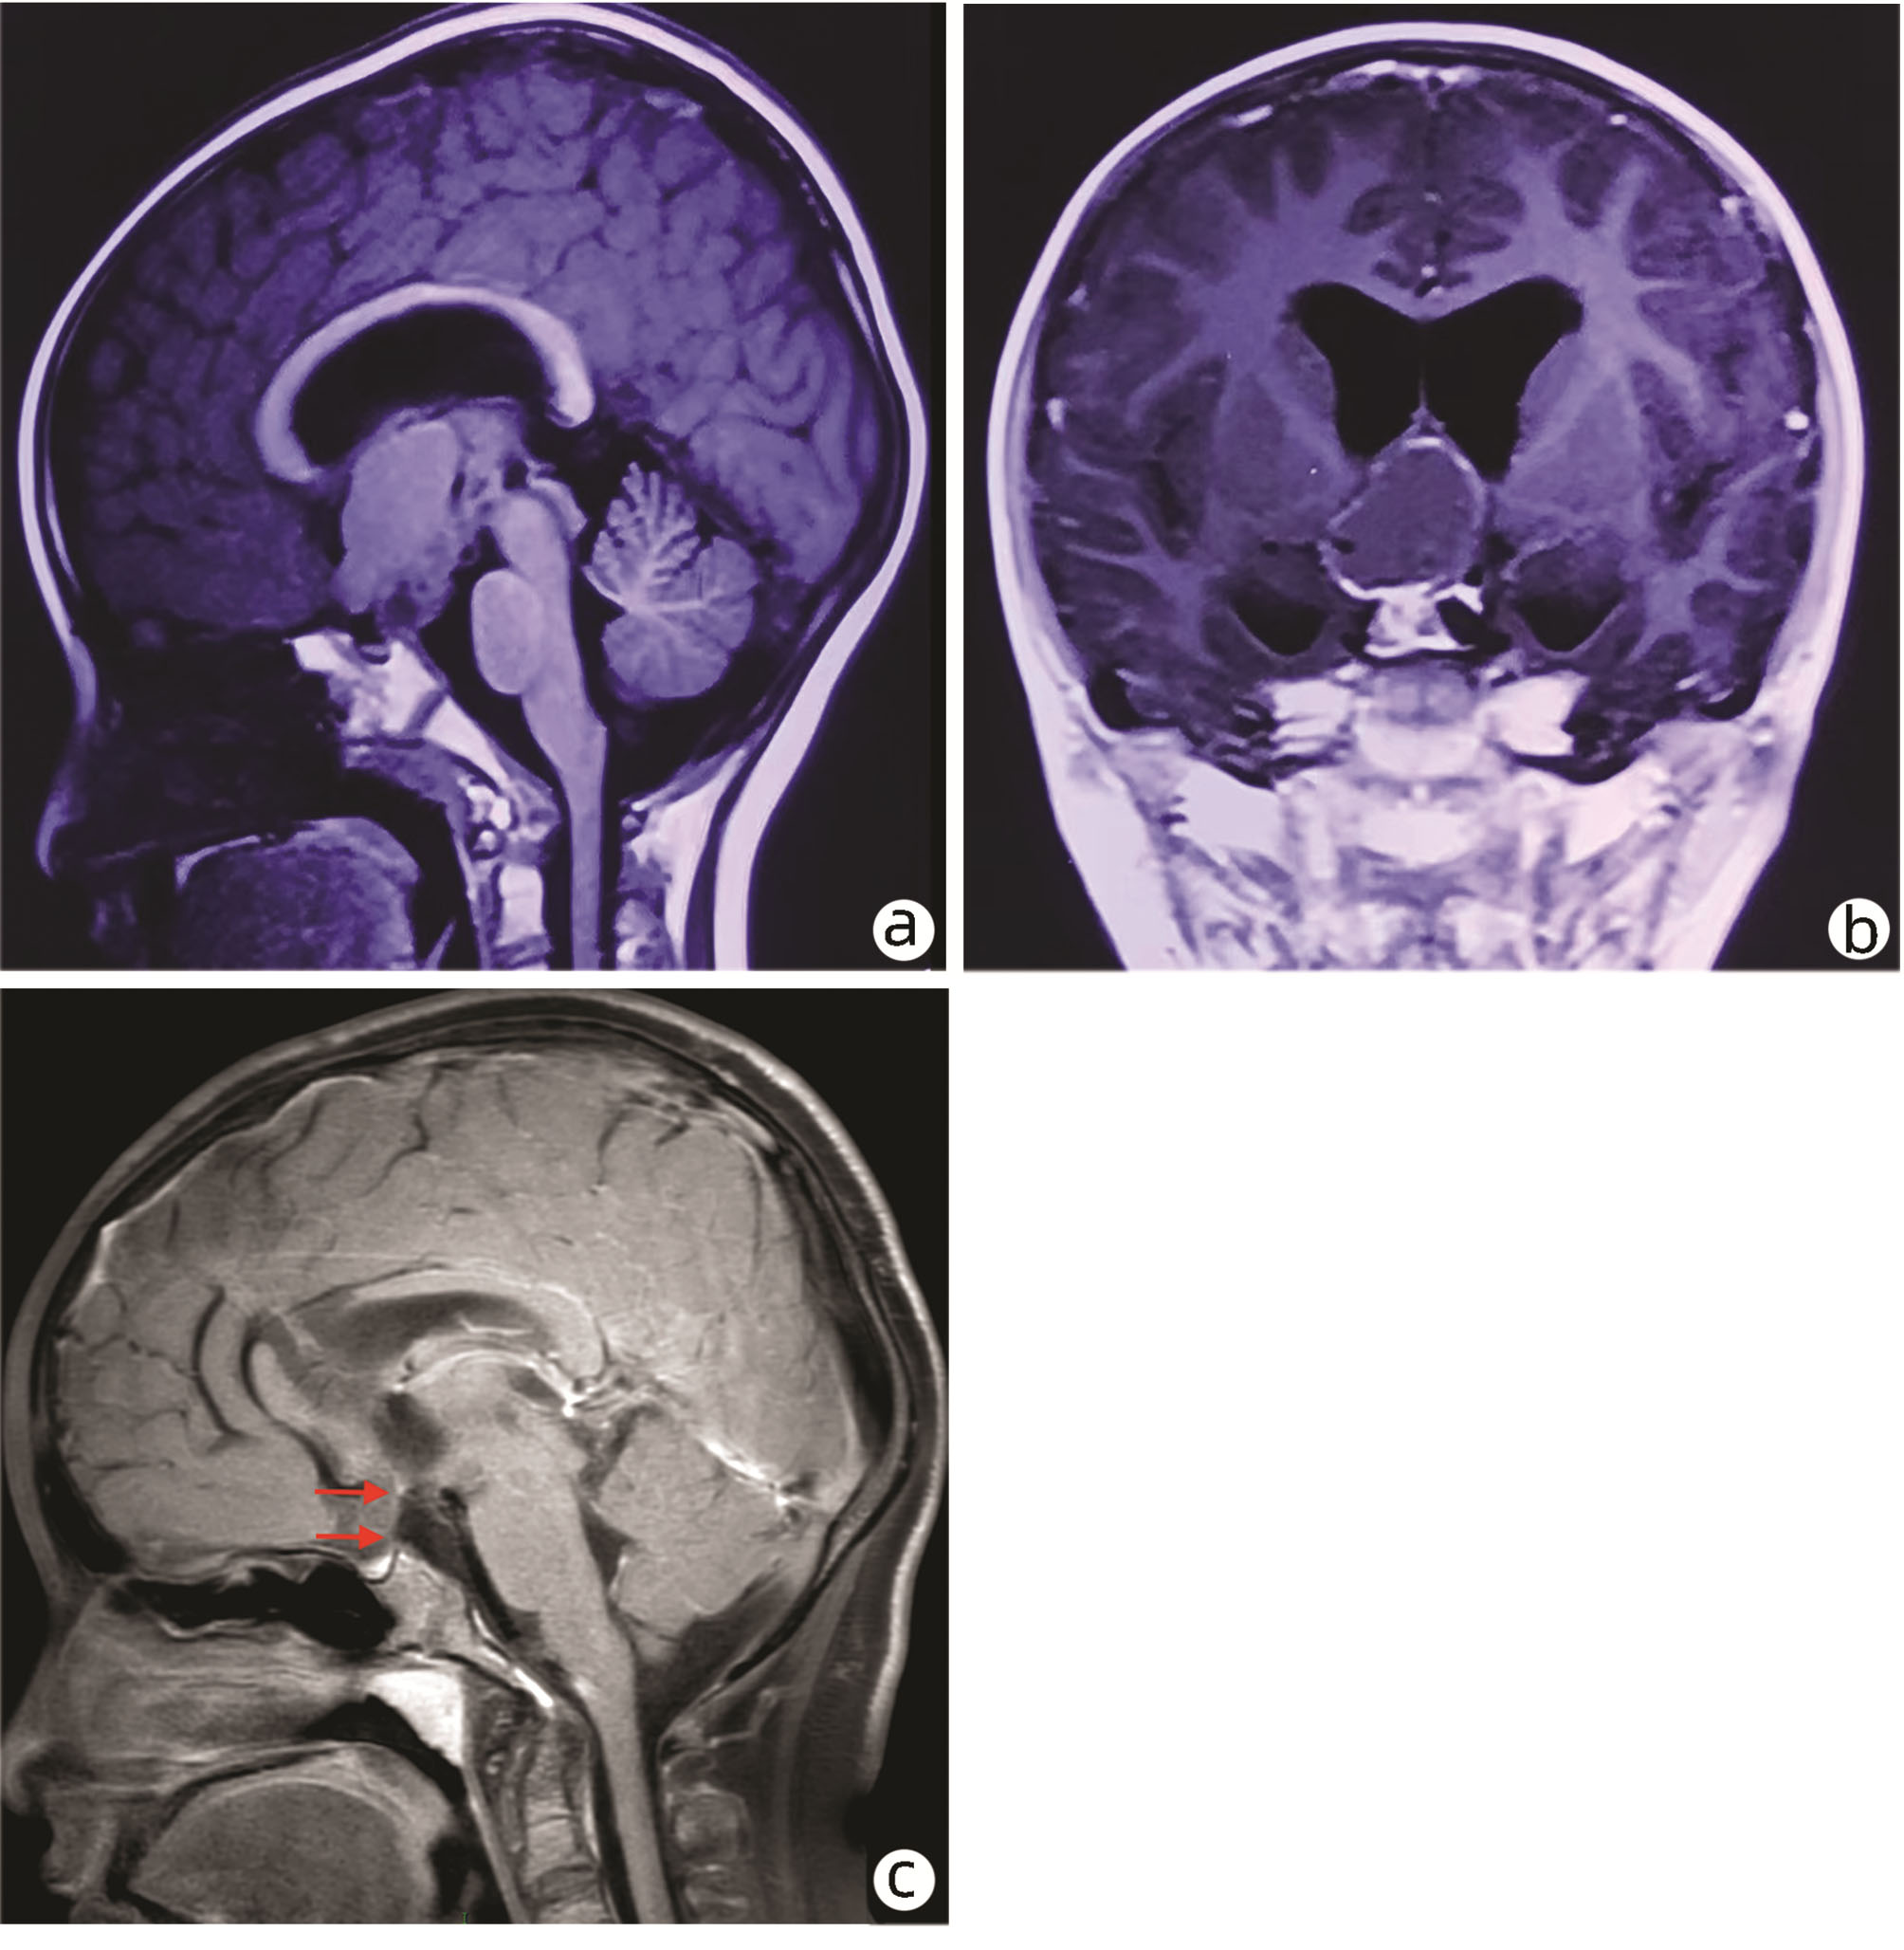

Hepatopulmonary syndrome after craniopharyngioma operation in children: A case report

Tingting DU, Hui YAO, Yakun LI, Xiaoli HUANG, Jie LUO

2022, 38(7): 1620-1625. DOI: 10.3969/j.issn.1001-5256.2022.07.030

Abstract(1022) HTML (325) PDF (2776KB)(75)

Abstract: